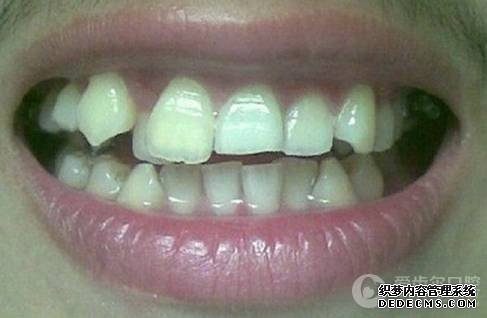

基本信息:项先生,29岁,IT,经朋友介绍就诊

患者自述:眼看快到而立之年,身边好友都已成家立业,可我依然孤身一人,难免有些落寞。可是因为牙齿不齐,让我总是缺乏自信,性格也变得内向腼腆,几次相亲都被心仪的女孩拒绝。为了不被自卑心吞噬,我决定通过牙齿正畸改变自己,给自己一次幸福的机会。

临床诊断:通过3D数字化全景机的拍片检查,患者上下牙排列拥挤,前牙受挤压向内歪斜,咬合关系异常,唇形尚可,颞下颌关节检查未见异常,无蛀牙、牙周疾病症状。经过和患者商量,选定自锁托槽矫正方案,调整牙间隙,恢复牙齿的正常排列,实现正常的咬合关系。

矫正前照片